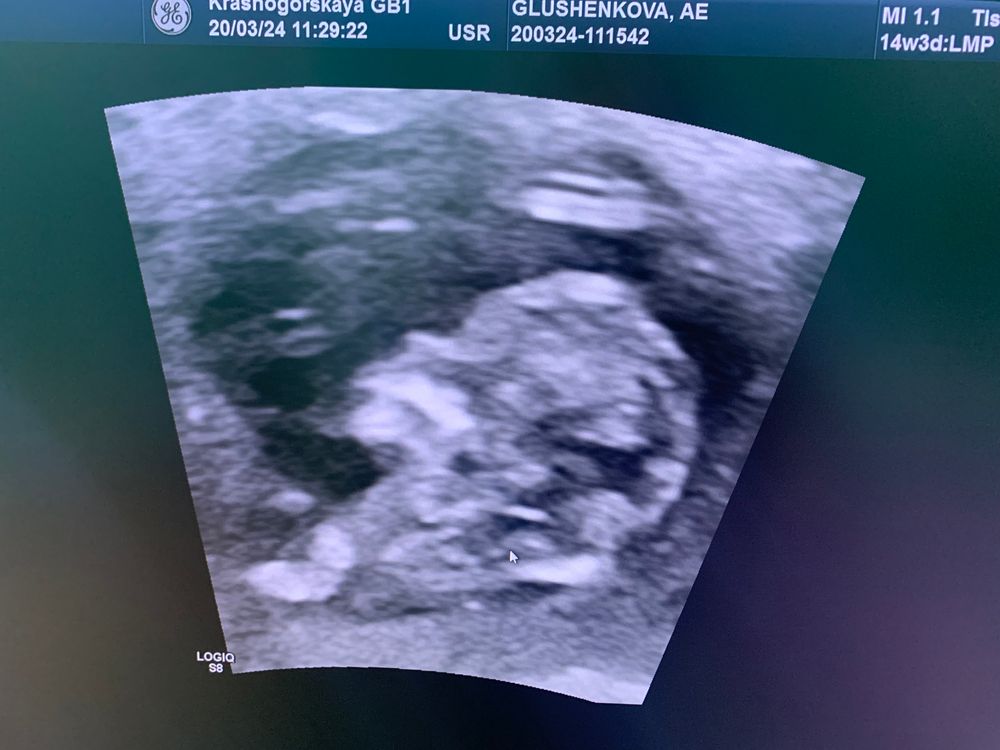

Первый скрининг …патология

Эва, еще может быть узистка не айс поэтому не видит) не знаю почему но на последнем фото мне кажется я отчетливо вижу и носик и носовую кость

Солнце, вот и я кажется все вижу,может конечно потому,что хочу но уже хз,возможно она долго меня крутила и малыш говорит как-то неудобно лежит

У вас есть носовая косточка, я ее вижу. Уверена, у вас все хорошо

Family, 🙏вот и мне кажется я ее вижу,спасибо ❤️

Александра , нос это важная часть 1 скрининга. Важно его только наличие, точечное например. автору сходить на экспертное узи и сдать нипт